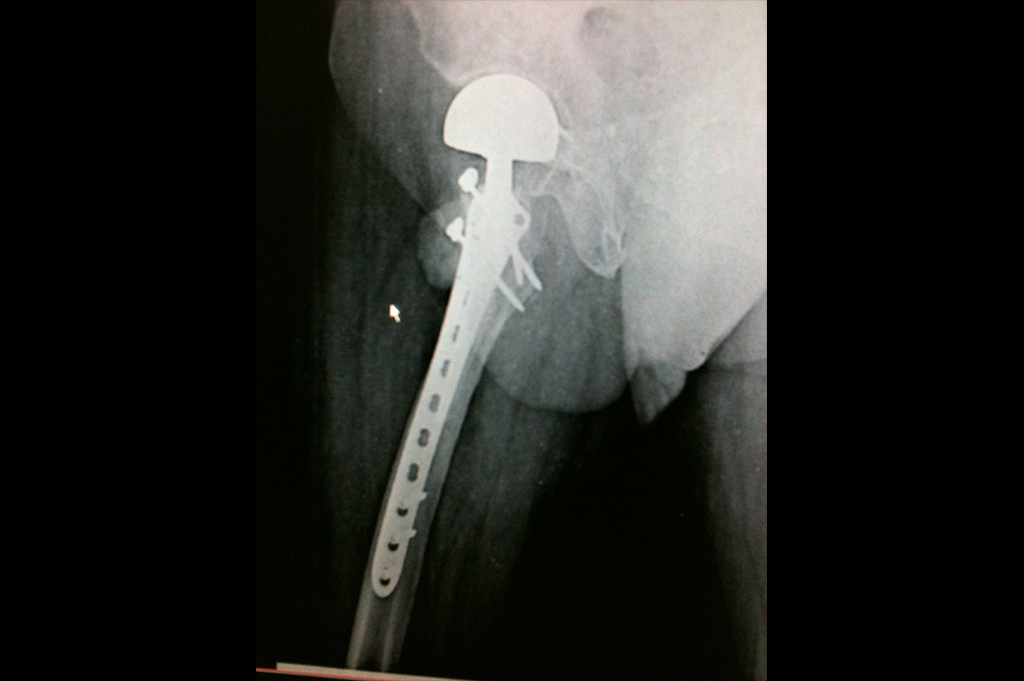

Intertrochanteric Fracture